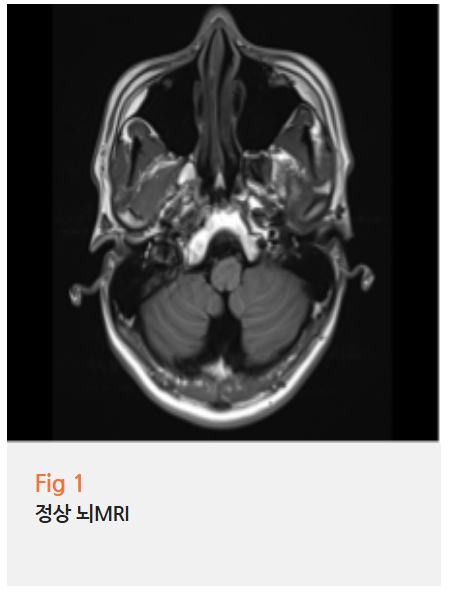

저는 주저 없이 당일 뇌 MRI 촬영을 결정했습니다.

"MRI요? 그게 필요할까요..."

환자분은 조금 놀라셨지만

안면신경마비는 뇌의 구조적 문제와 연결될 수 있어

반드시 확인이 필요하다고 설명드렸죠.

MRI 결과를 기다리는 그 30분이

저도 늘 긴장되는 시간입니다.

다행히 이분은 뇌에 기질적 문제는 없었습니다.

하지만 안면신경 자체에는

명확한 염증 반응이 관찰됐어요.